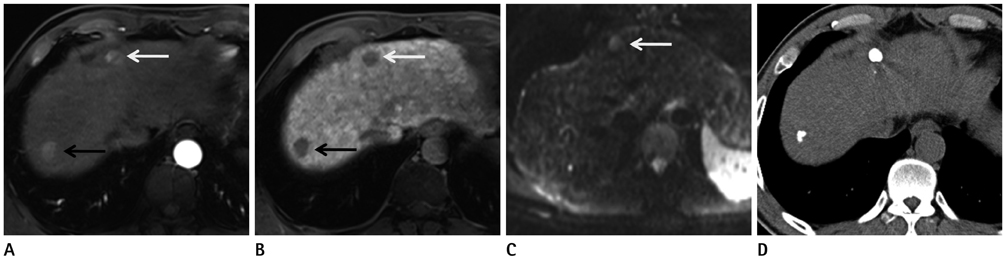

To compare diffusion-weighted imaging (DWI) and gadoxetic acid-enhanced (Gdx) magnetic resonance imaging (MRI), whether alone or in combination, for the detection of hepatocellular carcinoma (HCC) by using 3 T.

84 HCCs in 66 patients (57 men, 9 women; mean age 69.2 years) were examined using 3 T MRI. DWI (b values 0, 50, and 800 sec/mm2) and dynamic gadoxetic acid-enhanced MRI as well as hepatobiliary phase were performed. Images were retrospectively reviewed by two radiologists to compare the diagnostic performances of DWI and Gdx MRI alone and in combination for the detection of HCC. Alternative free response receiver operating characteristic analysis and comparison of sensitivities were used for statistical analysis.

The sensitivity of Gdx set (73/84, 87%) was significantly higher than that of DWI set (60.5/84, 72%) for both observers. The Az values of DWI and Gdx MRI for the detection of HCC were not statistically significant for either observer (Az for DWI = 0.818 and 0.864, Az for Gdx MR = 0.902 and 0.842, respectively, p = 0.107 for observer 1 and p = 0.738 for observer 2). The combination of both techniques did not increase the sensitivities of detecting HCC in either observer. When lesions smaller than 2 cm were considered, the DWI set yielded a significantly lower sensitivity as compared with either the Gdx set alone or the combination set.

Gadoxetic acid-enhanced MRI was better than DWI for detection the HCC by using 3 T MRI. The combination of DWI and Gdx MRI did not contribute to the successful detection of HCC.

Figure